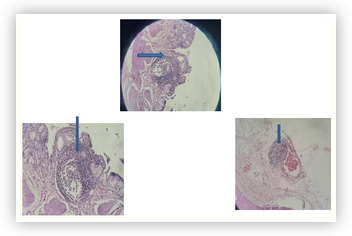

A Rare Case of Follicular Cholecystitis with Cholelithiasis

Menka Kapil, Maryem Ansari and Ram Daga.